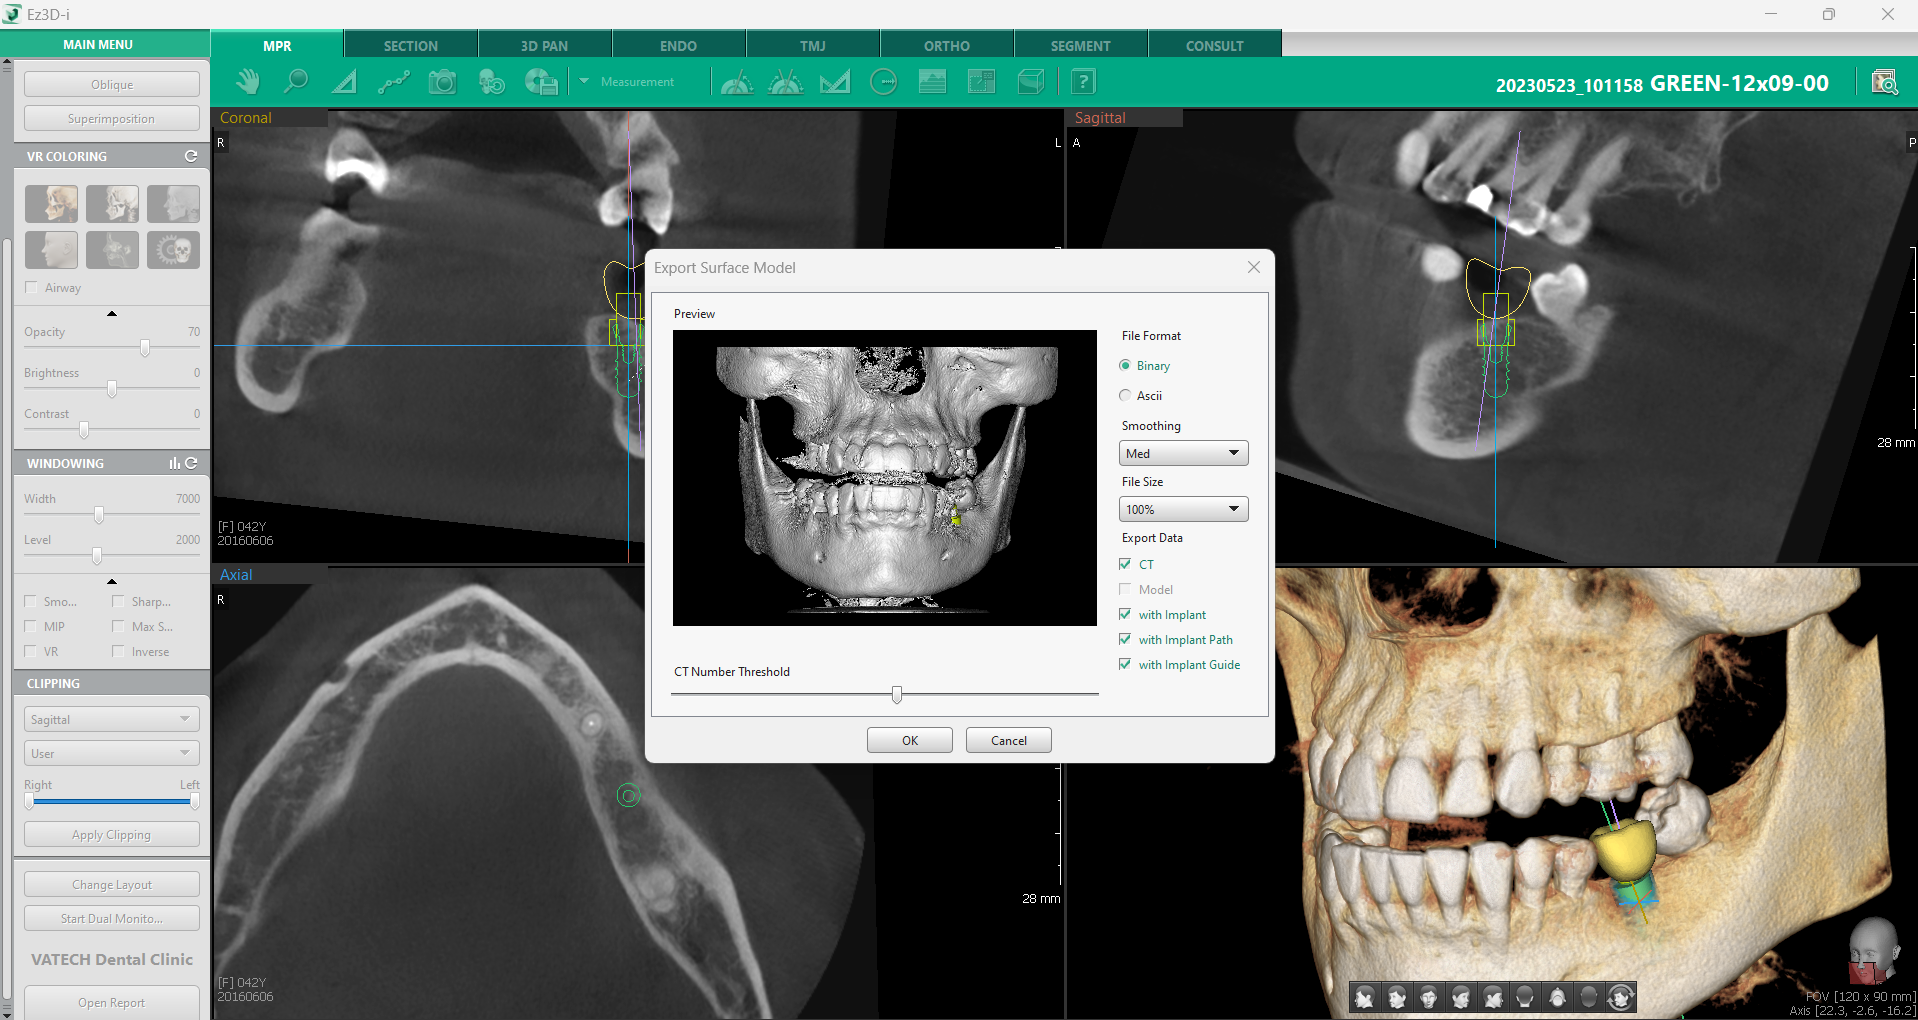

Odată ce toate ajustările au fost realizate, urmează exportarea modelului pentru integrarea cu sistemele CAD/CAM. Aceasta se face rapid, accesând meniul principal și selectând “Export Surface Model”. Caseta de dialog ghidează întregul proces, oferind opțiuni pentru formatul fișierului, nivelul de netezire, dimensiunea și tipul de date care urmează să fie exportate.